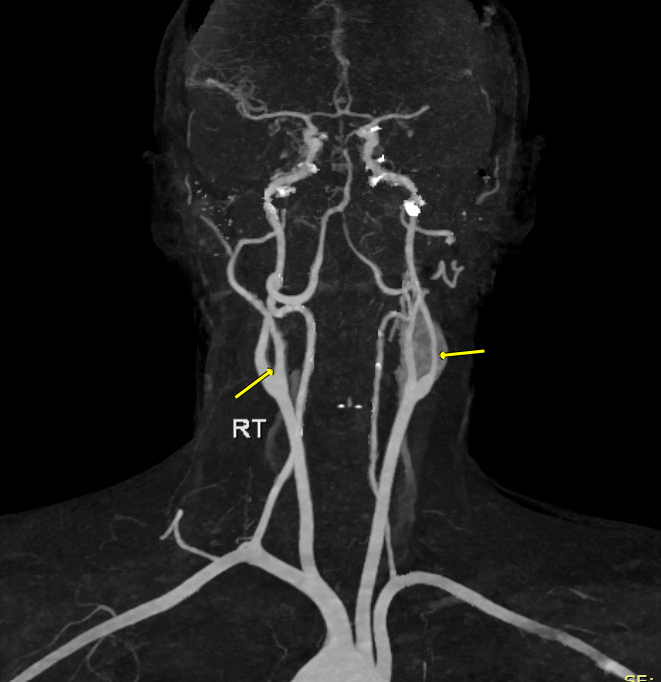

المنطقة التناسلية الذكرية تتلقى إمدادًا وفيرًا من الدم، والذي يتم توفيره بشكل رئيسي من خلال الشرايين الحرقفية. يؤدي تصلب الشرايين إلى انخفاض تدفق الدم إلى الأعضاء التي يغذيها. على سبيل المثال، إذا تأثرت الشريان الفخذي، الذي يغذي الساق، ستظهر أعراض مثل الألم ونقص التروية في الساق؛ وعندما يؤثر تصلب الشرايين على الشريان الأورطي أو الشرايين الحرقفية، سيؤثر ذلك على تدفق الدم إلى الساقين وكذلك إلى الحوض الذي يحتوي على الأعضاء التناسلية.

من أجل حدوث انخفاض كبير في تدفق الدم، يجب أن تتأثر كل من الشريان الأورطي البعيد والشرايين الحرقفية. يتميز متلازمة لاريش بتصلب شديد في الشريان الأورطي البعيد والشرايين الحرقفية المشتركة، مما يؤدي إلى انسداد كامل. ينتج عن ذلك أعراض مثل العرج المتقطع الثنائي في الساق والعجز الجنسي.